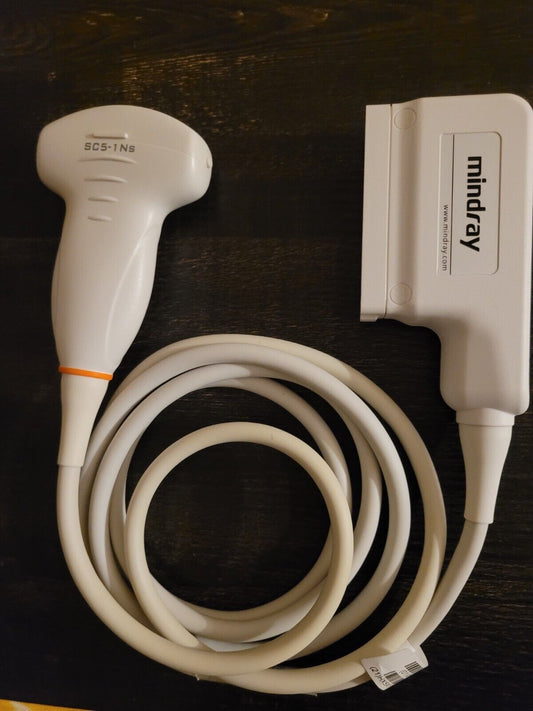

Mindray SC5-1Ns Convex Abdominal transducer Probe (Demo probe)

Regular price $1,199.00 USDRegular priceUnit price / per